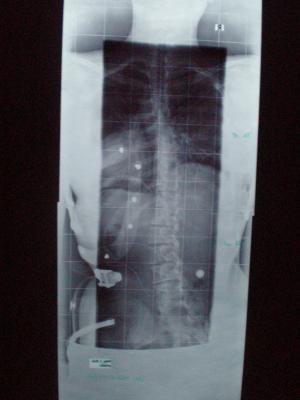

gestern hatte ich mein Röntgen im Korsett..

th. von 36° auf 19° im Korsett + Erhöhung 1.5 cm und

lu. von 50° auf 15° im Korsett + Erhöhung 1.5 cm :)

hätte ich nicht gedacht das man das noch von 50 auf 15 grad schafft ..

ich hatte eher damit gerechnet das die Grade im thorakalen Bereich weniger werden..aber naja..so ist auch gut :)

Ich hab die Röntgenbilder abfotografiert..

werd sie auch mal mitreinstellen..

th. 19° lu. 15° mit Korsett und mit Erhöhung 1.5 cm

th. 36°  lu. 50° ohne Korsett und ohne Erhöhung